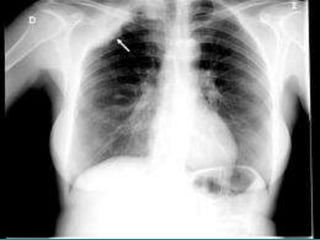

Radiografia de torax

En la radiografía simple de tórax se observó

una posible opacidad parahiliar derecha